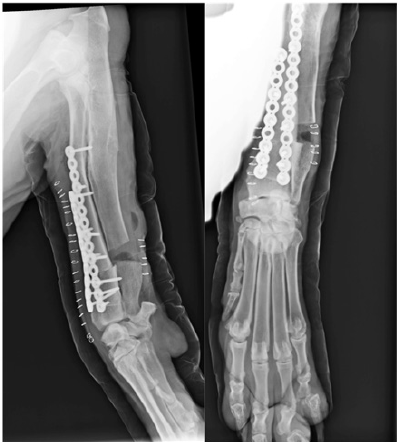

Follow-up radiographs (Figure 2C) were performed at 4, 8, 12, 16and 24weeks post-surgery, at which point no anomalies in bone healing were detected. Orthopedic examination revealed immediate correct alignment and normal weight bearing of the limb, with the resolution of lameness 16 weeks post-operatively. Three years postoperatively, an orthopedic exam and radiography were performed (Figure 2D). This revealed the satisfactory resolution of clinical signs with no lameness. At this time, elbow range of motion was normal. A minor reduction in carpal range of motion was detected but was non-painful.